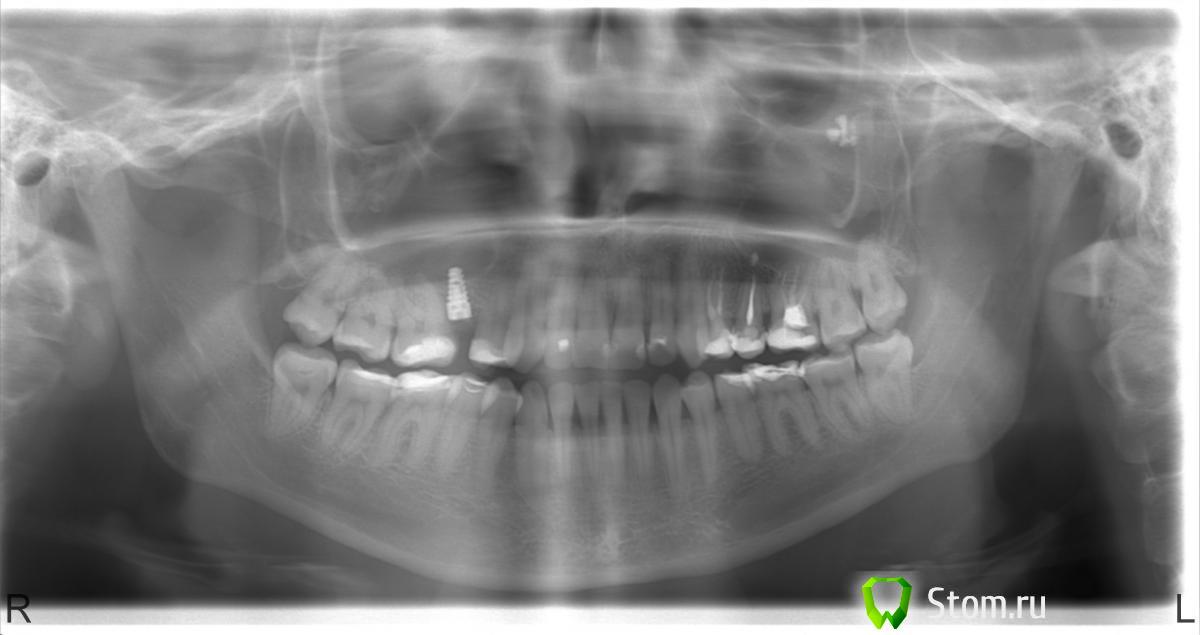

Rozettka Опубликовано 28 апреля, 2012 Автор Поделиться Опубликовано 28 апреля, 2012 Здравствуйте!Сегодня наконец прошла операция. Помотрите пжл снимок сразу после операции. Нормально стоит? Ссылка на комментарий

Bier Опубликовано 29 апреля, 2012 Поделиться Опубликовано 29 апреля, 2012 а у вас в самом деле там так мало места между 6 и 4 зубами? Ссылка на комментарий

Rozettka Опубликовано 30 апреля, 2012 Автор Поделиться Опубликовано 30 апреля, 2012 нет, на самом деле больше. Снимок немного искажает, самый первый снимок лучше отражает. Ссылка на комментарий

Rozettka Опубликовано 1 мая, 2012 Автор Поделиться Опубликовано 1 мая, 2012 Что скажете по поводу положения импланта? Очень важно ваше мнение Ссылка на комментарий

Bier Опубликовано 1 мая, 2012 Поделиться Опубликовано 1 мая, 2012 снимок искажает, если места между зубов достаточно, то все ок. Ссылка на комментарий